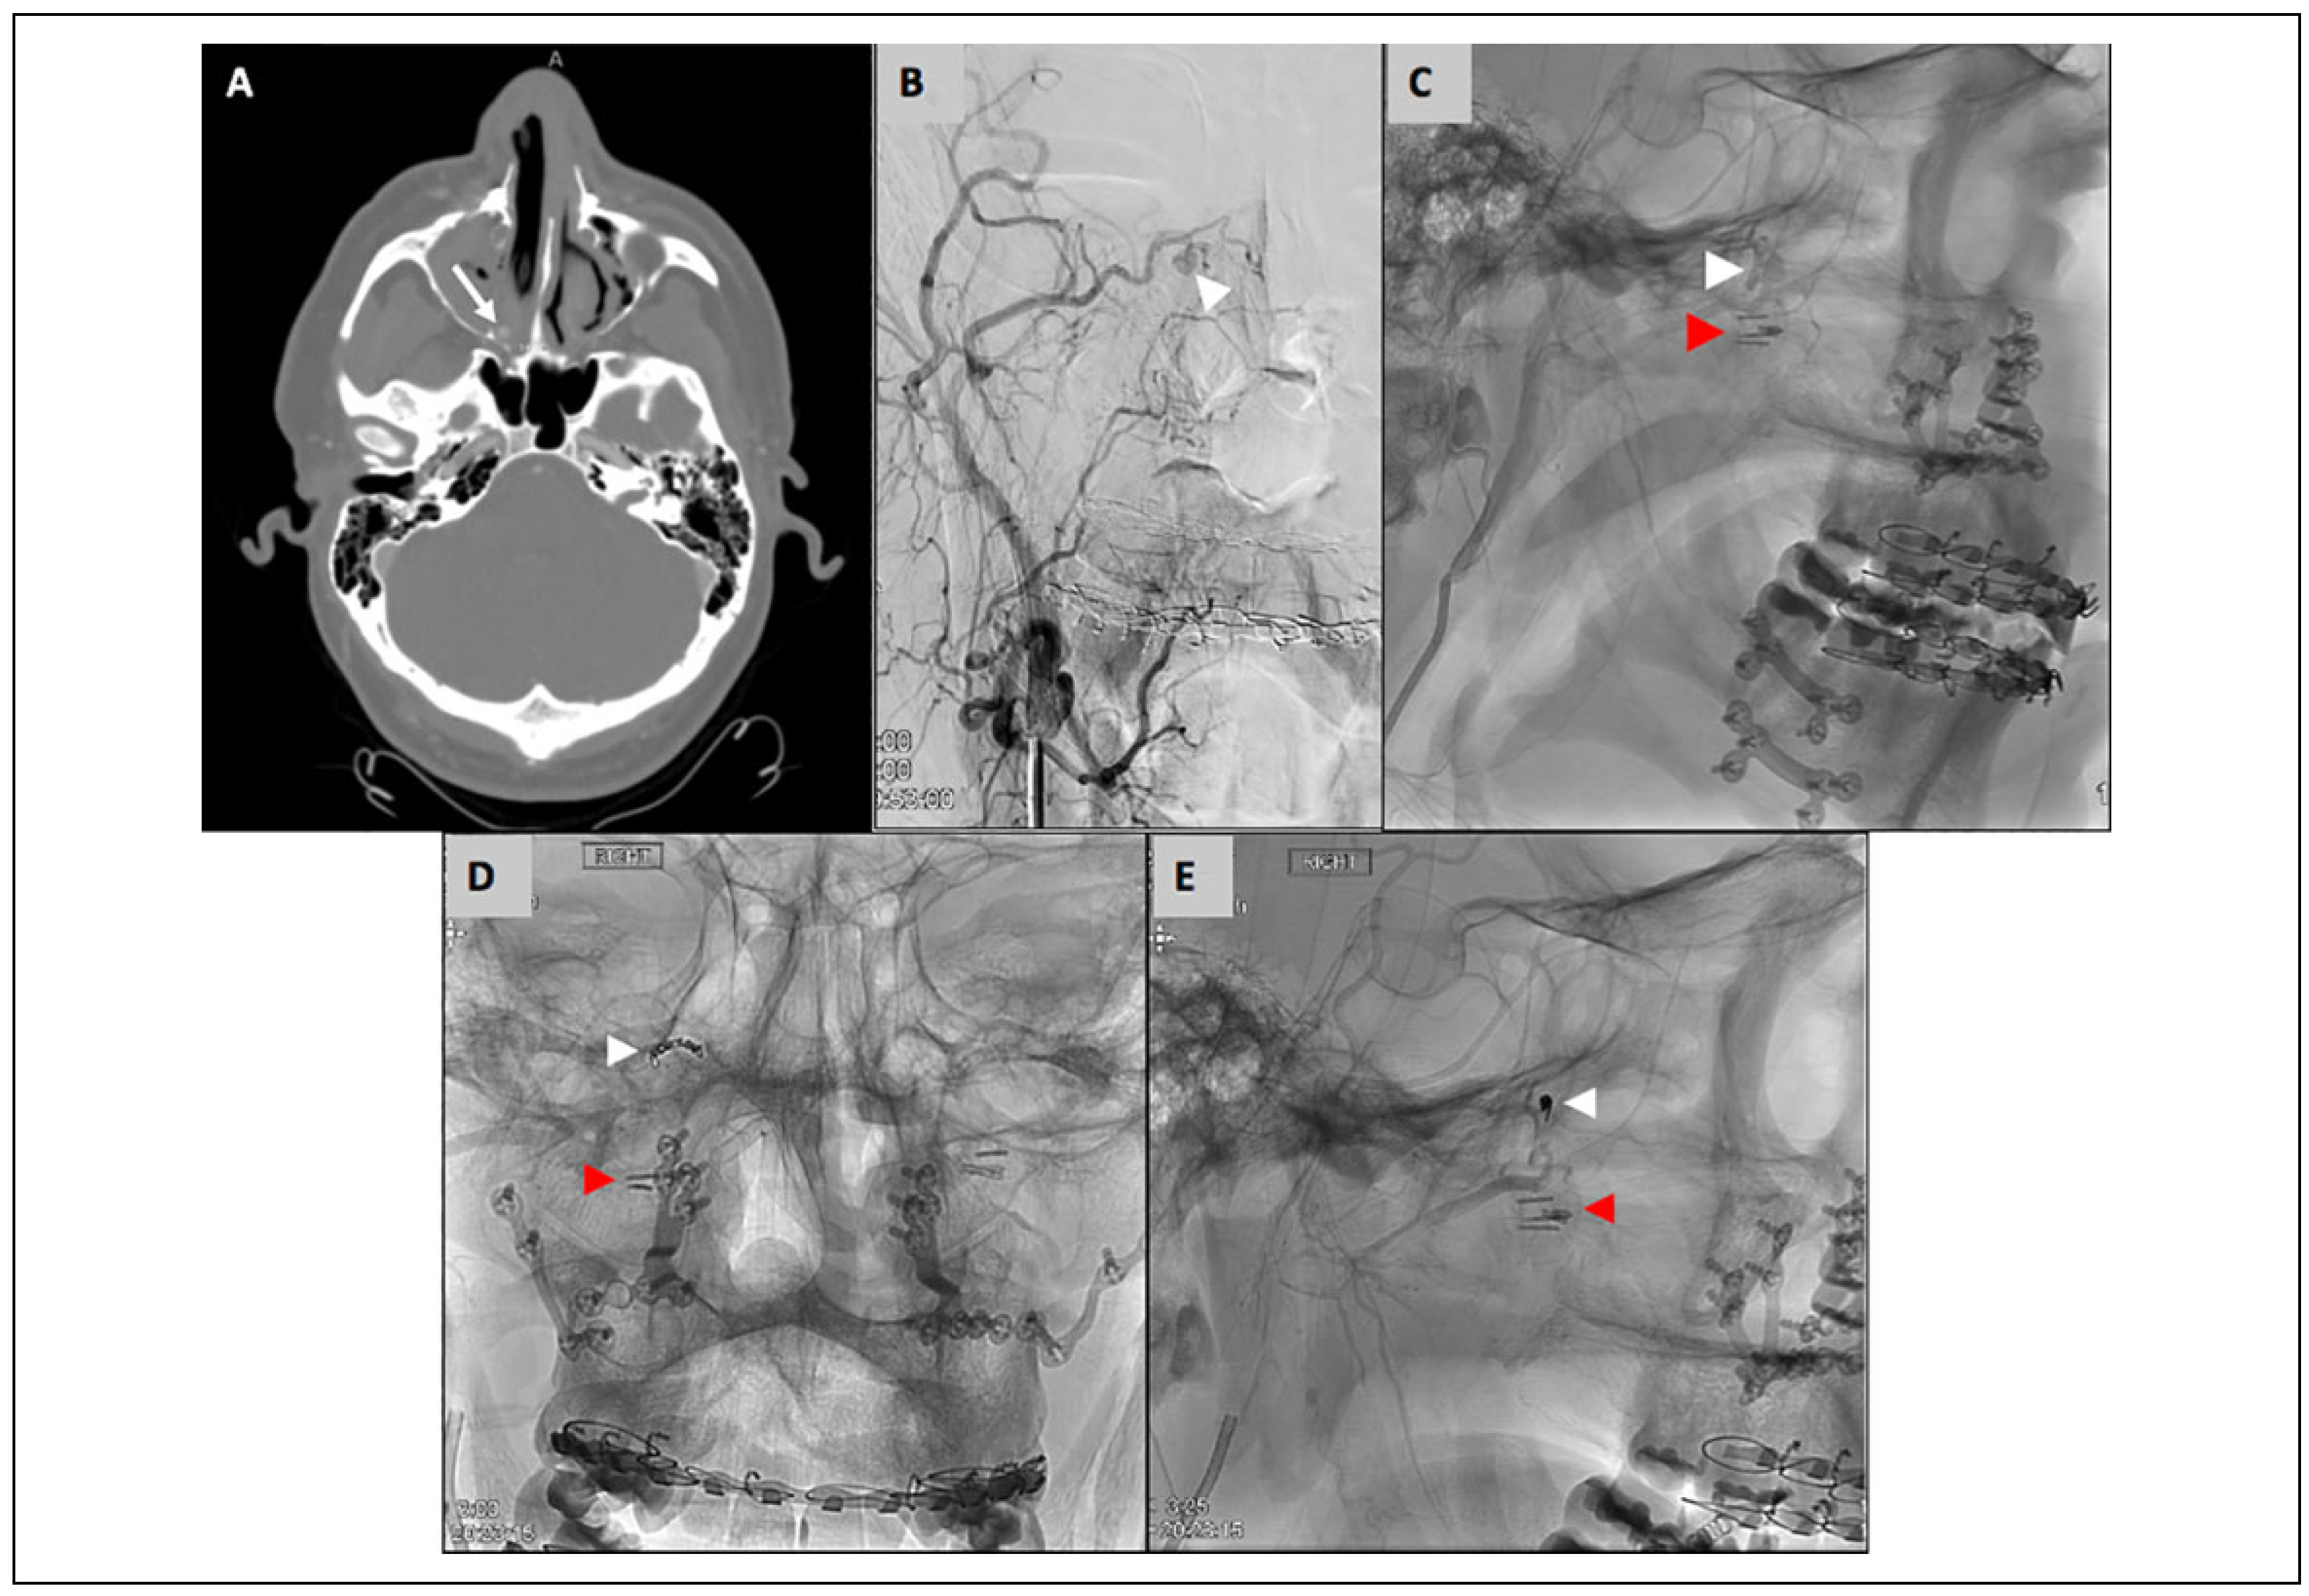

Case 2

A 33-year-old male with obstructive sleep apnea underwent Le Fort 1 osteotomy with bilateral sagittal split osteotomies for maxillomandibular advancement. Notably, the descending palatine arteries were ligated intraoperatively, which is routinely done by the operating surgeon. The patient was discharged on postoperative day 1. He then presented to the emergency department 15 days postoperatively with moderate right-sided bright red nasal bleeding and mild right facial swelling. The right nasal cavity was packed with a 7.5 cm rhino-rocket. He was hemodynamically stable and had no other complaints at this time. Laboratory data were notable for a hemoglobin of 10.2 g/dL, which had decreased from a hemoglobin of 15.5 g/dL on the day of surgery. A CT angiogram was obtained, which showed a right sphenopalatine artery pseudoaneurysm (3 mm) with active blush (Figure 5). Neurointerventional radiology was consulted, who ultimately embolized the pseudoaneurysm with 2 coils. The coils measured 1.5 mm × 3 cm and 1 mm × 3 cm. The nasal packing was left in place and he was observed overnight. He was discharged on postoperative day 1 and returned to clinic on postoperative day 3 for removal of the nasal packing. At 3 months postoperatively, there was no recurrent bleeding.

Figure 5. Case 2; A. CT angiogram (axial view) of right sphenopalatine artery pseudoaneurysm (3 mm) with active blush (white arrow), with rhino-rocket in place. B. & C. Angiography (frontal and sagittal view) of sphenopalatine artery pseudoaneurysm (white arrowhead) and clips on the descending palatine arteries placed intra-operatively (red arrowhead). D. & E. Angiography post-embolization (frontal and sagittal view) showing coils in sphenopalatine artery pseudoaneurysm (white arrowhead) and clips on the descending palatine arteries placed intra-operatively (red arrowhead).